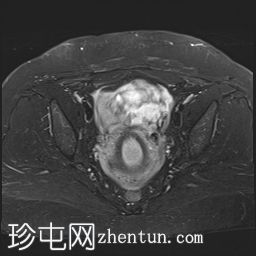

冠状位

T2加权像

可见子宫外腹腔内妊娠囊,内含胎儿组织。

该妊娠囊向后推移子宫,并与剖宫产瘢痕凹陷处紧密相连。

该妊娠囊与相关肠袢无法分离。可见其与性腺血管密不可分,且性腺血管明显突出。

胎盘位于妊娠囊后方,紧贴子宫前壁。

沿妊娠囊下缘可见一处异质性局灶性积液,最大轴向尺寸约为 8.4 × 5.5 cm,T1 加权像呈异质性高信号,T2 加权像呈异质性中等信号,T1 脂肪抑制序列未见信号下降,提示为血液成分。该积液压迫膀胱。

可见周围脂肪间隙呈条索状改变。

子宫体积增大,后倾,子宫内膜厚度约 1 cm,子宫下段前壁可见局灶性变薄(既往子宫瘢痕)。子宫连接区完整,未见肌层肿块。可见子宫内膜腔边缘有血性分泌物。